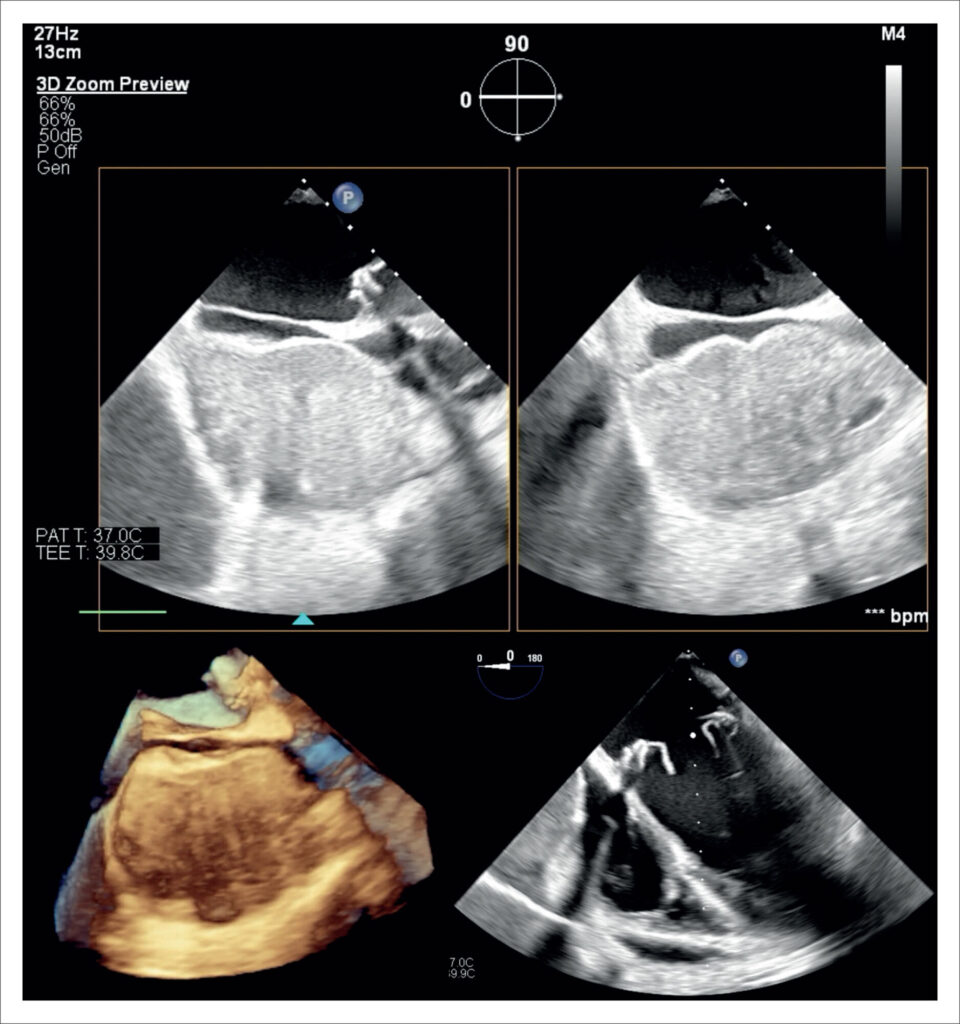

Hematoma Pericárdico com Dor Torácica e Tamponamento em Pós-Operatório Tardio de Cirurgia Cardíaca

Este relato descreve uma apresentação atípica de hematoma pericárdico manifestado como dor torácica intensa no 23° dia de pós-operatório, com evolução rápida para instabilidade hemodinâmica. O ecocardiograma desempenhou um papel fundamental no diagnóstico e na condução do caso para um desfecho favorável.